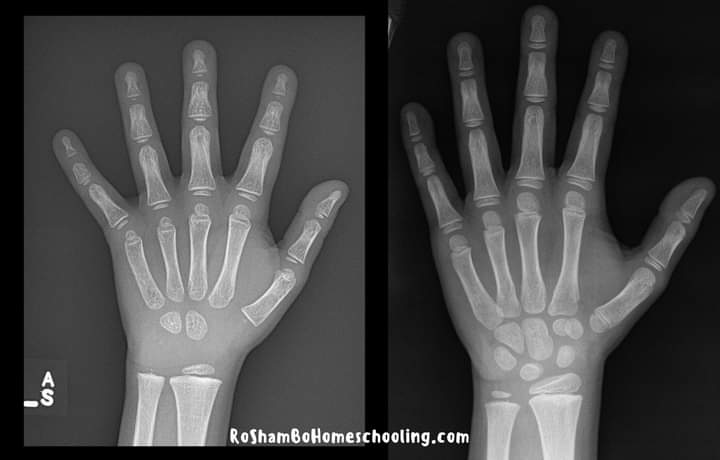

Shihni dallimin midis duarve të një 7 vjeçari (në të djathtë) dhe dorës së një 4 vjeçari në kopsht (në të majtë).

Sepse duart e tyre janë ende duke u rritur dhe nuk janë të plota dhe ende po marrin formën e tyre përfundimtare. Pra, çfarë duhet të bëjmë në këtë pikë? Lejoni femijet të luajnë në forma të ndryshme, luajnë jashtë, brenda, pra në cdo vend dhe në cdo mënyrë. Të gjitha këto gjëra do të ndihmojnë muskujt e tyre të rriten dhe të kompletohen. Kur të jenë të gatshëm fizikisht për të shkruar, do të shkruajnë! Nuk ka nevojë të nxitoni me fëmijën tuaj prindër apo edhe ju mësues.